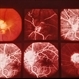

- 14-year-old white female. Congenital. 20/40.